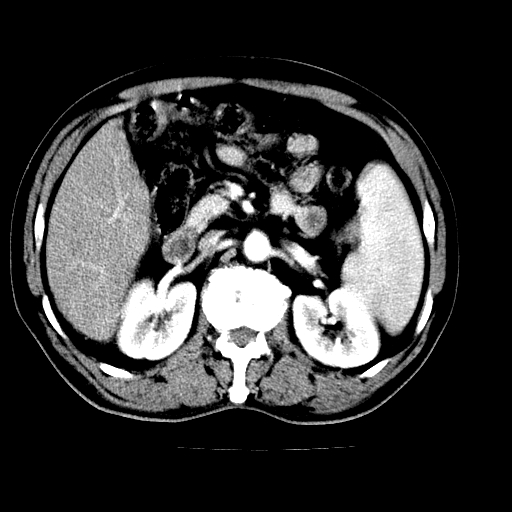

男,66岁,上腹部不适、黄染一周。彩超示:肝左叶占位,肝内胆管扩张,胆总管扩张,胆总管占位?

肝左叶不规则软组织肿块影,边缘不规整邻近肝实质受累分界不清;肝内胆管(左叶)明显扩张成“软藤状”,诊断:肝左叶胆管细胞癌。

肝左叶占位性病变,并胆管扩张,符合胆管细胞癌ct表现,门脉左支受累,左肾囊肿。窗宽太窄了,其他的看不清

左叶胆管细胞癌累及胆总管,门脉左支受侵,慢性胆囊炎胆结石,左肾小囊肿

肝左叶不规则软组织肿块影,边缘不规整邻近肝实质受累分界不清;肝内胆管(左叶)明显扩张成“软藤状”,诊断:肝左叶胆管细胞癌。胆囊钙乳症。